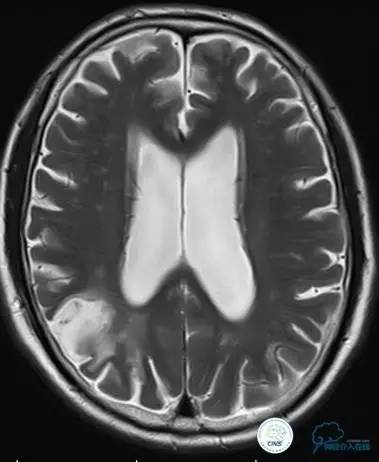

术后即刻和6天后CT,患者无明显临床症状。

半年后复查造影,无支架内再狭窄,可见弹簧圈,患者恢复至自己柱杖行走。